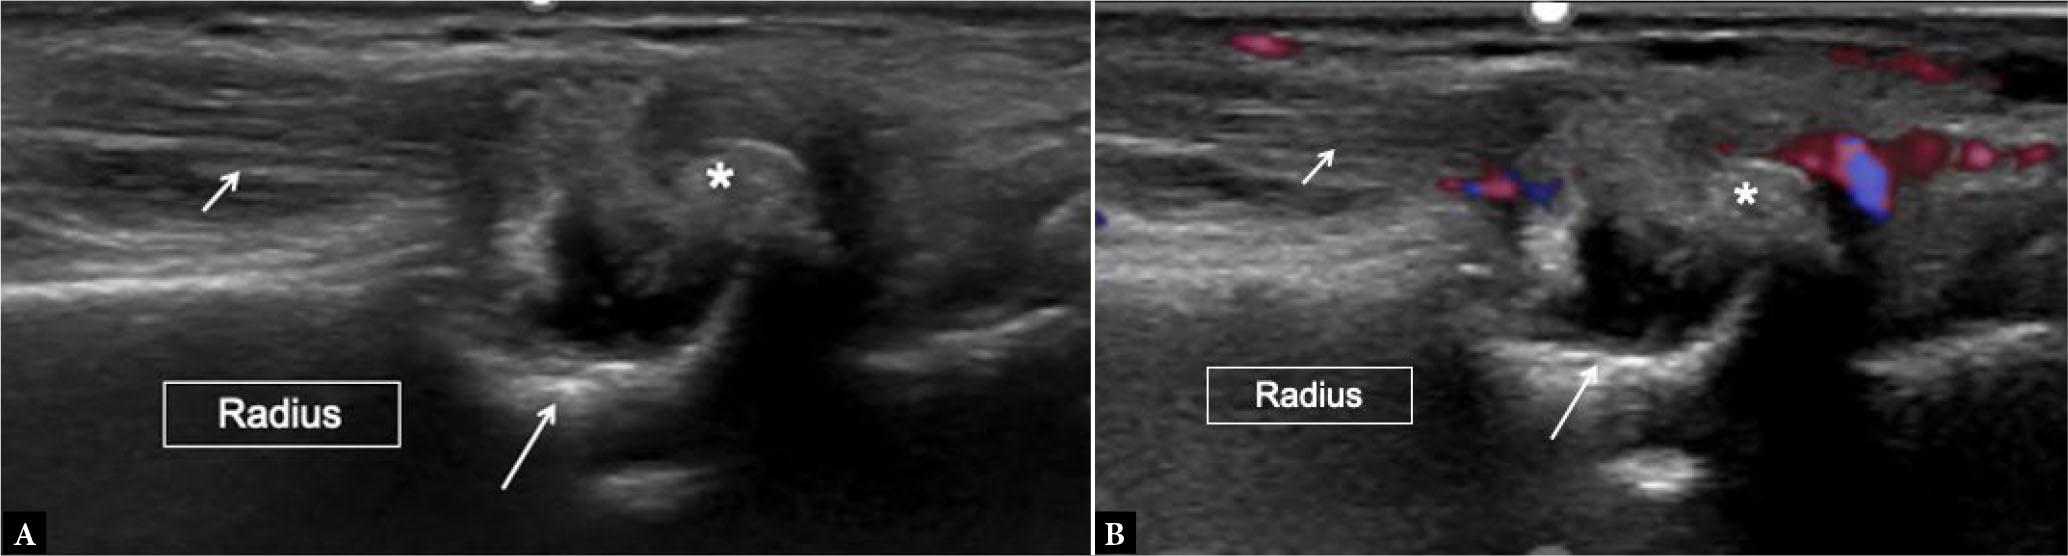

Fig. 25.

Gout. Long-axis grayscale (A) and power Doppler (B) US image at the wrist joint shows large overhanging erosion in the radius (long arrows) adjacent to extensor digitorum tendon (short arrows). There is a large echogenic tophus overlying the erosion (asterisks) with surrounding power Doppler signal (B)